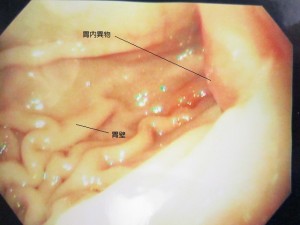

内視鏡中の胃内の様子です。

幽門部に異物が見えます。